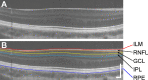

Purpose: To test whether ganglion cell layer (GCL) and inner plexiform layer (IPL) topography is altered in albinism.

Methods: Optical coherence tomography scans were analyzed in 30 participants with albinism and 25 control participants. Horizontal and vertical line scans were acquired at the fovea, then strip registered and averaged. The Duke Optical Coherence Tomography Retinal Analysis Program was used to automatically segment the combined GCL and IPL and total retinal thickness, followed by program-assisted manual segmentation of the boundary between the GCL and IPL. Layer thickness and area under the curve (AUC) were calculated within 2.5 mm of the fovea. Nasal-temporal and superior-inferior asymmetry were calculated as an AUC ratio in each quadrant.

Results: GCL and IPL topography varied between participants. The summed AUC in all quadrants was similar between groups for both the GCL (P = 0.84) and IPL (P = 0.08). Both groups showed nasal-temporal asymmetry in the GCL, but only participants with albinism had nasal-temporal asymmetry in the IPL. Nasal-temporal asymmetry was greater in albinism for both the GCL (P < 0.0001) and the IPL (P = 0.0006). The GCL usually comprised a greater percentage of the combined GCL and IPL in controls than in albinism.

Conclusions: The GCL and IPL have greater structural variability than previously reported. GCL and IPL topography are significantly altered in albinism, which suggests differences in the spatial distribution of retinal ganglion cells. This finding provides insight into foveal development and structure-function relationships in foveal hypoplasia.